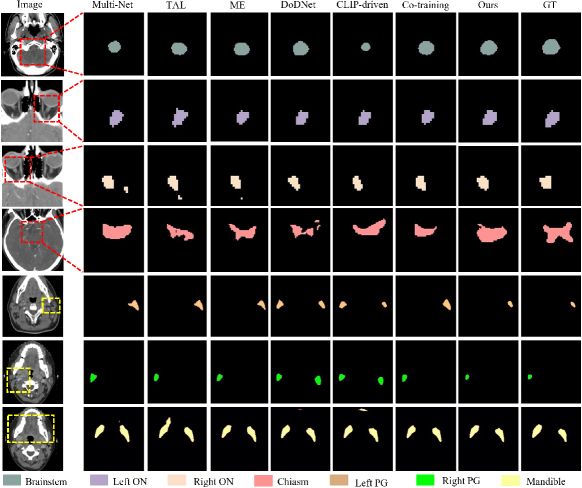

Tables I, II, III and IV present the segmentation results for the head and neck, chest, abdomen, and pelvis, respectively. Figs. 4, 5, 6 and 7 provide visualizations of these methods. The following conclusions can be drawn from these results:

Unified segmentation models generally outperform Multi-Net, as indicated by combined DSC and ASSD metrics. Among channel adjustment methods, ME outperforms TAL by leveraging non-overlapping organ annotations across datasets. The conditionally-guided DoDNet achieves sub-optimal results in the chest and abdomen but performs poorly in the head and neck and pelvis, particularly for the chiasm and parotid glands; The method also struggles to distinguish between symmetrical structures (e.g., parotid glands and humerus), as noted in COSST [4]. The CLIP-driven method performs poorly across all regions, especially for less frequent organs and structures like the chiasm. The Co-training method, based on two stage pseudo-labeling, achieves competitive results, particularly in the pelvis. Overall, our method outperforms others across all regions, especially for small organs like the chiasm and elongated organs like the esophagus. Visually, our method aligns more closely with GT, avoiding the segmentation errors of channel adjustment and the issues with symmetric structures in conditional guidance methods.

The effectiveness of our method has been demonstrated through the experiments on diverse datasets encompassing the head and neck, chest, abdomen, and pelvis, which has consistently achieved superior performance in each of these regions, surpassing the state-of-the-art methods (see Tables I, II, III and IV). Additionally, visual results show that our method’s segmentation results closely matches the ground truths (see Figs. 4, 5, 6 and 7). According to the results obtained by different methods, incorporating organ-specific priors, as evidenced in TAL [8] and ME [9], and employing pseudo-labelling through Co-training [5], effectively enriches the supervisory signals, thereby enhancing segmentation outcomes. Conditional information-guided methods excel with specific organs but struggle with smaller structures, and they are unable to differentiate between symmetric structures, such as the left and right parotid glands and the left and right humers, as shown in the fifth column of Figs. 4 and 7. Although CLIP-driven method has achieved significant success in the segmentation of abdominal organs[12], it relies on large datasets for training, and most of the images pre-trained by CLIP are natural images. Therefore, further exploration is needed to adapt this method to medical imaging.